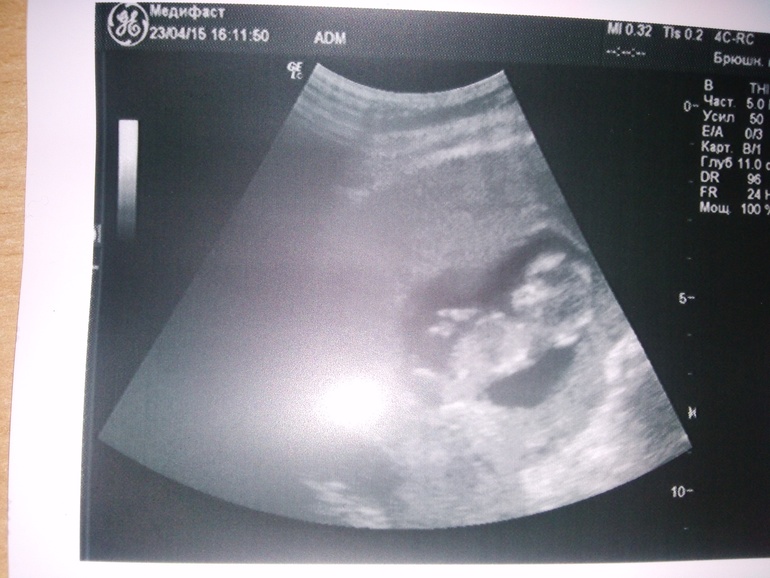

УЗИ в 12 недель

сходила сегодня)) все хорошо, малявка растет и барахтается, правда мне не показали((( но зато врач все подробно рассказывал и постоянно улыбался, говорил, что крохе не нравится, что мы на него смотрим и он все время уворачивается)))

пол не сказал, хоть и смотрел минут 10 в разные стороны, только улыбнулся и загадочно сказал - нет, пока ничего не могу сказать....ну и наше первое фото "человеческое"))) за качество извиняюсь. с телефона плоховато видно...

почему???)))) ну как ты это поняла??? и мне муж вчера сказал))) говорит, смотри между ног ничего нет))) ну тут на фото вообще плохо видно, так как фото со вспышкой было...на оригинале лучше...но я не представляю что там вообще можно понять???